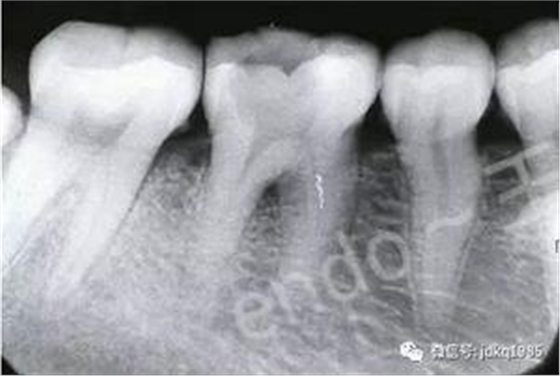

臨床病例報(bào)告:患者為30歲女性,因后牙自發(fā)性疼痛于當(dāng)?shù)蒯t(yī)院行“根管治療”,治療過(guò)程中出現(xiàn)“斷針”,建議轉(zhuǎn)診,遂來(lái)我院就診。X線檢查可見(jiàn)46近中根管中上段約3mm的高密度影像,其余根管內(nèi)未見(jiàn)充填影像,根尖區(qū)見(jiàn)密度減低透射影。由于患者存在根尖病變,且分離器械位于根管中上段,因此我們給患者擬定了根管內(nèi)分離器械取出的治療方案。

術(shù)前X線片可見(jiàn)近中根管內(nèi)分離器械